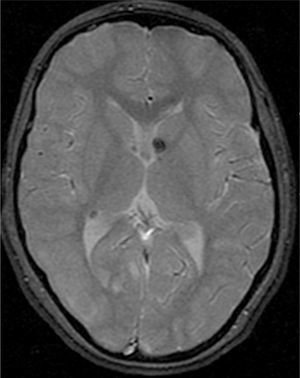

Los síntomas neurológicos, presentes en el 85% de los casos, son la principal causa de morbimortalidad3. La epilepsia y el retraso cognitivo están comúnmente asociados a lesiones cerebrales, incluyendo hamartomas glioneuronales (también llamados tuberomas), lesiones de la sustancia blanca y astrocitomas de células gigantes subependimarios9.

Las resonancias magnéticas (RM) cerebrales evaluadas han sido revisadas de forma independiente por el mismo examinador de la especialidad de Neurorradiología y se estudiaron las siguientes variables: número de tuberomas, localización supra o infratentorial, el número de lóbulos cerebrales con lesiones, el número y la lateralización de tuberomas con quistes, las líneas de migración radial de la sustancia blanca, los nódulos subependimarios y los astrocitomas de células gigantes. Los pacientes efectuaron los estudios de RM en equipos GE Signa 1.5T y en RM Philips Achieva 3.0T TX (3 pacientes), en el Departamento de Neurorradiología del CHP. Después de obtenida la imagen localizadora en el plano sagital, para identificar las comisuras anterior y posterior, se han adquirido imágenes en paralelo al plano intercomisural: FLAIR, T2 SE, T2 *, T1 SE y T1 SE tras contraste.

Se consideraron tuberomas con quistes subcorticales las lesiones con una señal similar al del líquido cefalorraquídeo en todas las ponderaciones y con un anillo hiperintenso alrededor en T2. Los tuberomas o nódulos subependimarios calcificados han presentado una hiposeñal en T2 y T2*. Una vez que la cantidad o el número de tuberomas en el parénquima encefálico son indicados como el mejor marcador de gravedad de epilepsia y de la función cognitiva1, se efectuó una evaluación cualitativa por medio la frecuencia de tuberomas. En cada lóbulo cerebral, la densidad de tuberomas se relaciona con la carga de lesión cerebral obtenida por la evaluación del número total de tuberomas y de la afectación de cada lóbulo por los tuberomas. Se consideró como elevada carga de lesión la afectación de todos los lóbulos por tuberomas, en pacientes con número total de tuberomas más de 15. No han sido evaluados la densidad o el volumen de tuberomas por técnica cuantitativa de segmentación automática de tuberomas por inaccesibilidad a software apropiado.

El 74,3% (26) de las RM disponibles han sido revisadas en todos los lóbulos cerebrales en el 76,9% (20) de los pacientes, en los cuales se identificaron más de 15 tuberomas, es decir, una elevada carga de lesión. En el 96,2% (25) de los enfermos se observaron líneas de migración radial (fig. 1). Estaban presentes nódulos subependimarios en el 84,6% (22), la mayoría de los cuales con calcificación y, en 3 casos, con captación de contraste (fig. 2). En el 23,1% (6) de los enfermos se encontraron tuberomas infratentoriales. Siete casos presentaban tuberomas con aspecto quístico (26,9%), 6 de los cuales en localización yuxtacortical y uno infratentorial (fig. 3). Es de referir un caso con probable astrocitoma de células gigantes, bajo control dimensional, en la región del agujero de Monro, sin signos de hidrocefalia (fig. 4). Ninguno de los enfermos presentaba atrofia focal.